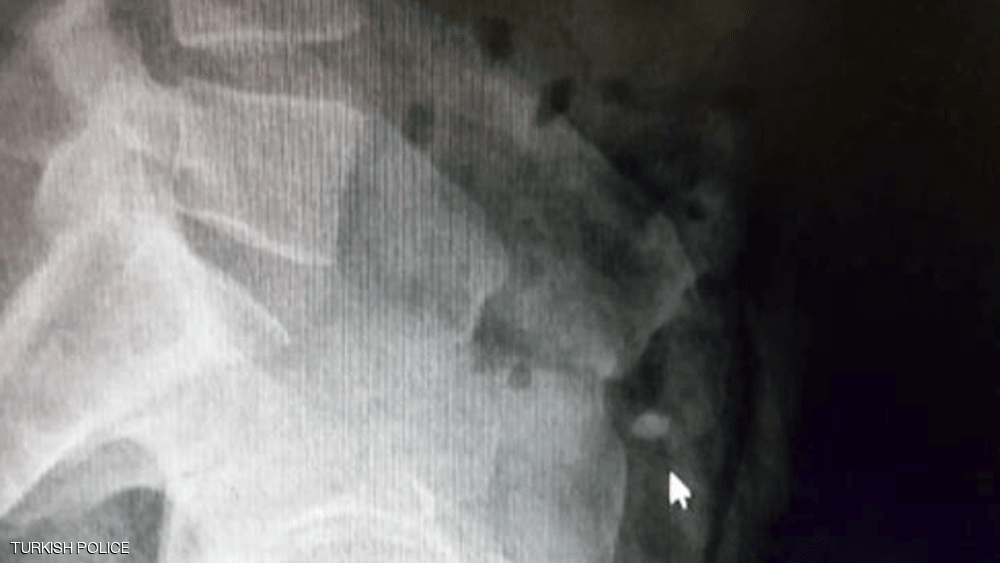

وأمرت الشرطة بنقل السارق إلى المستشفى، من أجل إجراء عملية جراحية للعثور على الخاتم، ما لم يعد الايرلندي الخاتم بـ"الطريقة الطبيعية".

وتابعت وسائل إعلام تركية "رحلة" الخاتم، لحظة بلحظة لمدة يومين كان خلالها اللص ينتظر في المستشفى بعدما تناول أدوية تسهّل الإخراج، وذلك تحت حراسة الشرطة.

وقد قفز مرارًا في المستشفى لتحريك الخاتم في أحشائه لمدة 36 ساعة، لكن جهوده كانت بلا جدوى، وبعد ذلك لجأت السلطات إلى استخراج الألماس عبر عملية جراحية.